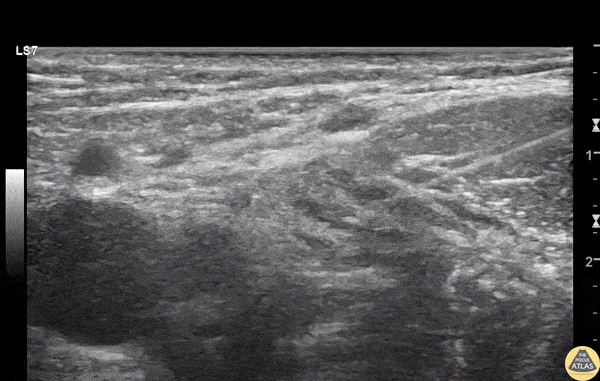

A teenage female patient arrived to the ED via EMS after she was truck by a car, sustaining multiple serious injuries, including a midshaft femur fracture which was significantly displaced. She required multiple rounds of IV analgesics, so a fascia iliaca block was performed to augment pain control. Shown here, the needle is seen entering from the lateral aspect through the iliacus muscle, injecting anesthetic just deep to the fascia iliaca. The femoral artery and vein are seen medial to this at the left of the image. The patient had improvement in pain level, and was able to be admitted to the ICU for further care. Dr. Kate Simeon, PGY1, and Dr. Nik Matsler, PGY4 Denver Health Residency in Emergency Medicine